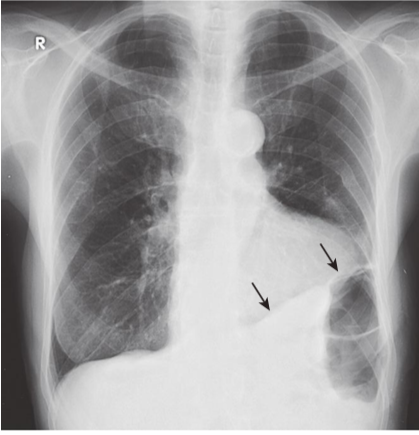

Scarring producing blunting of the left costophrenic angle.

Scarring (due, for example, to previous infection, surgery, or blood in the pleural space) sometimes produces a charac- teristic “ski-slope appearance” of blunting (black arrows), unlike the meniscoid appearance of a pleural effusion. This fibrosis would not change in appearance or location with changes in the patient’s posi- tion, as free-flowing pleural fluid would.